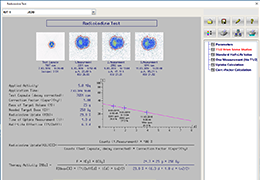

ANYTHINK 经导管主动脉瓣膜置换术分析系统